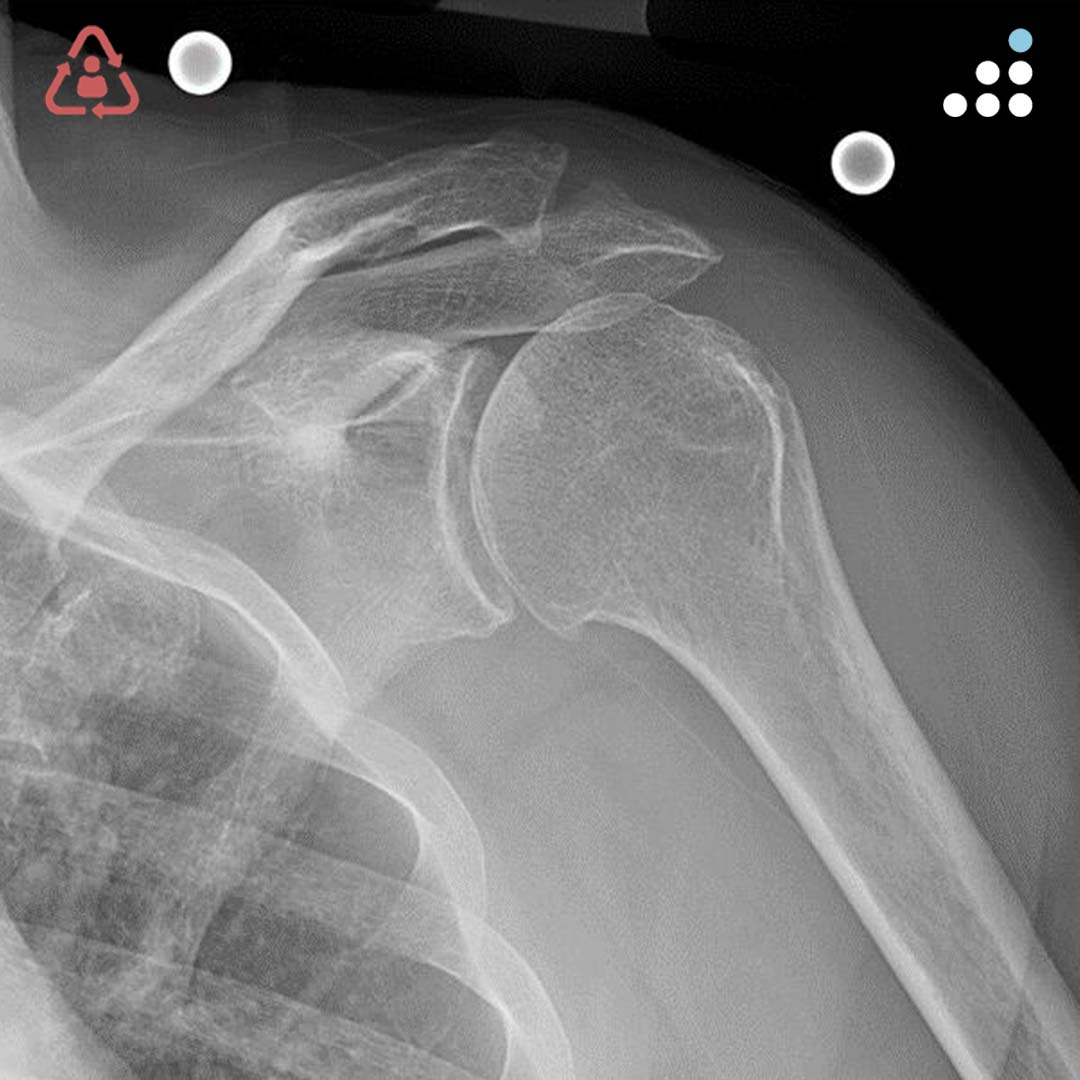

@orthobullets @KPSCALnews @rkh_md @DrMarecek @DeformityDoc @jamesablairMD @FractureDoc @stevemchale @traumaticum @DrFraneNicholas I am concerned about the +Fleck/flake sign. Get MRI or ultrasound to rule out a triceps rupture. If torn, I would perform ORIF and Triceps repair, after restoring the underlying metabolic issues. If the triceps is not torn, then would treat non-operatively.